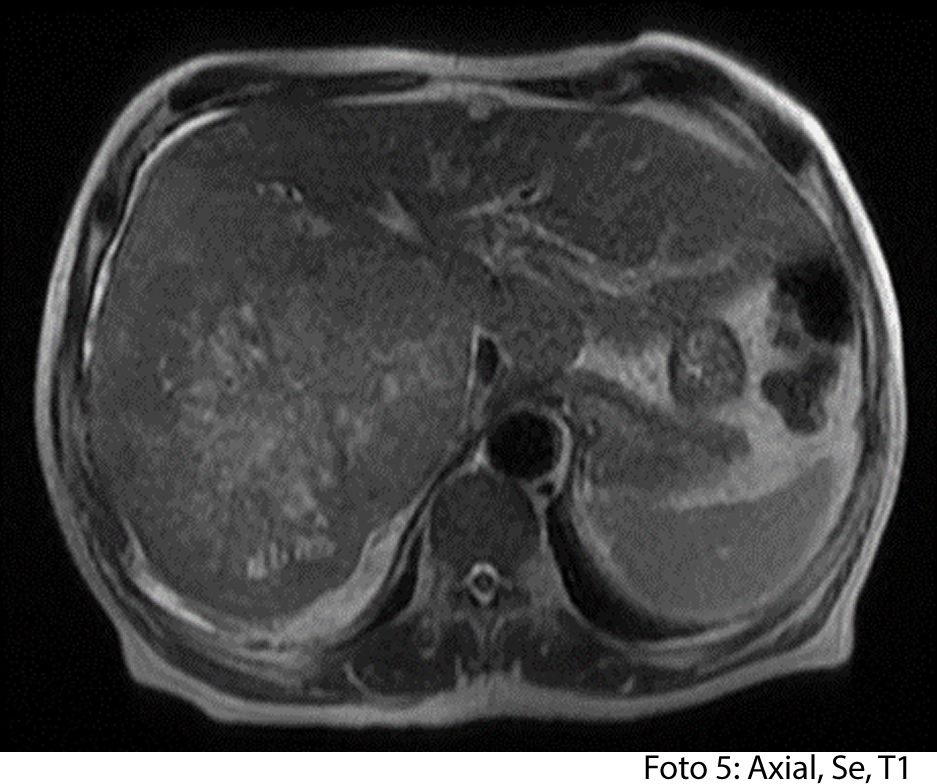

HALLAZGOS IMAGENOLOGICOS

• HEPATOCARCINOMA FIBROLAMINAL QUE COMPROMETE TODO EL LÓBULO DERECHO DEL HÍGADO

Es un método utilizado en el cual podemos observar una gran masa localizada en los segmentos del hígado también se puede medir el diámetro de la masa, el hepatocarcinoma también puede presentar focos hemorrágicos y además podemos captar de manera heterogénea el medio de contraste intravenoso. En los hepatocarcinomas podemos ver obstruyendo parcialmente la vena porta. Adenomegalias los cuales nos indican Los hallazgos como primera posibilidad diagnóstica, carcinoma hepatocelular fibrolamelar (CHC-FL).